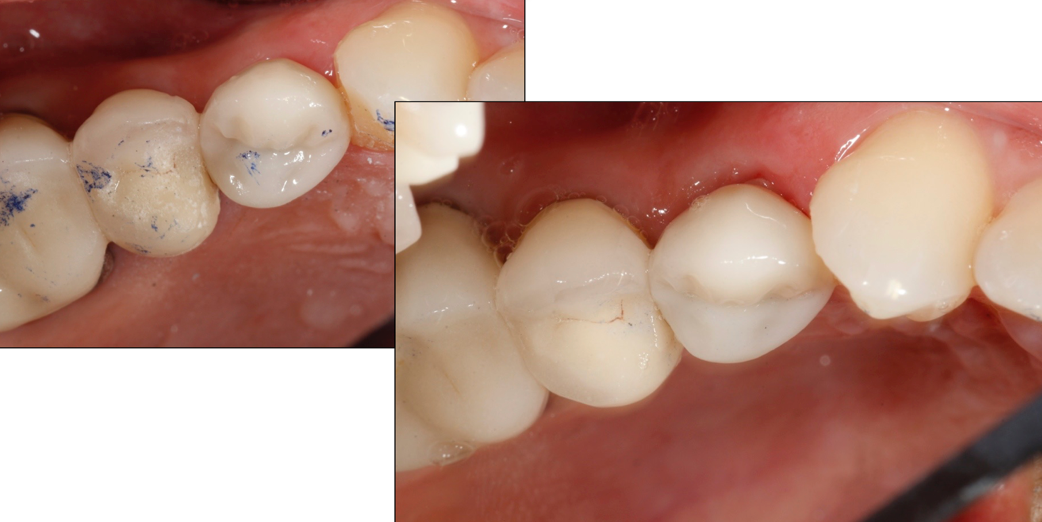

The milled restoration (Fig. 9) was crystallized and glazed in an Ivoclar Vivadent Programat CS2 oven.

Figs. 10-11

Fig. 9

The restoration was seated (Figs. 10-11), contacts and occlusion checked, and luted into place with Ivoclar Vivadent SpeedCem composite luting cement.